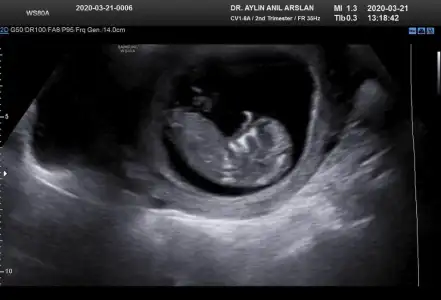

11+3 ama cok net değil gibi sanki yinede Bi tahmin isterim daha 5 hafta sonra öğrencez mecbur 😪

• IMG-20200321-WA0010.webp

IMG-20200321-WA0010.webp

25,9 KB · Görüntüleme: 44

• IMG-20200321-WA0011.webp

IMG-20200321-WA0011.webp

25,8 KB · Görüntüleme: 41

• IMG-20200321-WA0012.webp

IMG-20200321-WA0012.webp

25,8 KB · Görüntüleme: 40